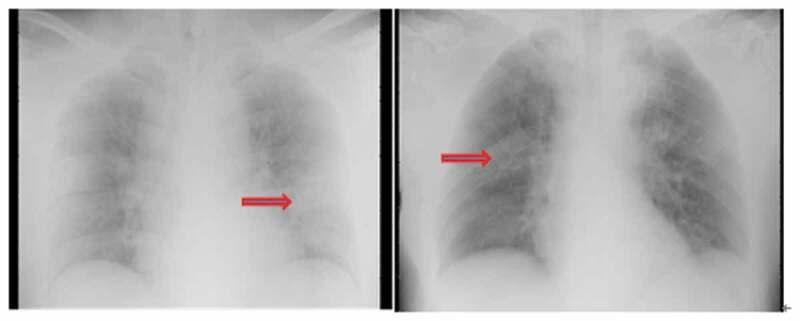

Since its outbreak in Wuhan, Hubei Province China, 2019-coronavirus infected disease (COVID-19) had been widely spread all over the world, the control of which calls for a better understanding of its epidemiology and clinical characteristics. We included 12 confirmed cases of COVID-19 in First Affiliated Hospital of Jilin University from 23 January 2020 to 11 February 2020, which were retrospectively analyzed for epidemiological, demographic, clinical, laboratory, and radiological features. All the patients were confirmed by nucleic acid detection, the average age of whom was 45.25 years (range, 23-79 years). Most patients had a history of Wuhan traveling or had contact with Wuhan travelers or infected cases. Obvious family cluster was observed. Clinical manifestations included fever (12/12), fatigue (10/12), cough (6/12), sore throat (4/12), headache (3/12), and diarrhea (2/12). Only three out of eight patients had pneumonia manifestation on radiography. Most patients had a normal white blood cell (WBC) count and normal or reduced lymphocyte (LY) count. Pneumonia changes were observed in all the four patients who underwent a chest CT scan. Only one elderly patient developed severe pneumonia, while all the rest were mild disease and had a self-limiting course.

自 2019 年 12 月湖北省武汉市爆发以来,新型冠状病毒感染的肺炎(COVID-19)已在全球范围内广泛传播,其控制需要更好地了解其流行病学和临床特征。我们纳入了 2020 年 1 月 23 日至 2 月 11 日吉林大学第一附属医院的 12 例确诊 COVID-19 病例,对其流行病学、人口统计学、临床、实验室和影像学特征进行回顾性分析。所有患者均经核酸检测确诊,平均年龄为 45.25 岁(范围 23-79 岁)。大多数患者有武汉旅行史或与武汉旅行者或感染病例接触史。观察到明显的家庭聚集现象。临床表现包括发热(12/12)、乏力(10/12)、咳嗽(6/12)、咽痛(4/12)、头痛(3/12)和腹泻(2/12)。仅 8 例患者中有 3 例放射学表现为肺炎。大多数患者的白细胞(WBC)计数正常,淋巴细胞(LY)计数正常或减少。接受胸部 CT 扫描的 4 例患者均出现肺炎改变。只有一位老年患者发展为重症肺炎,而其余均为轻症,具有自限性病程。